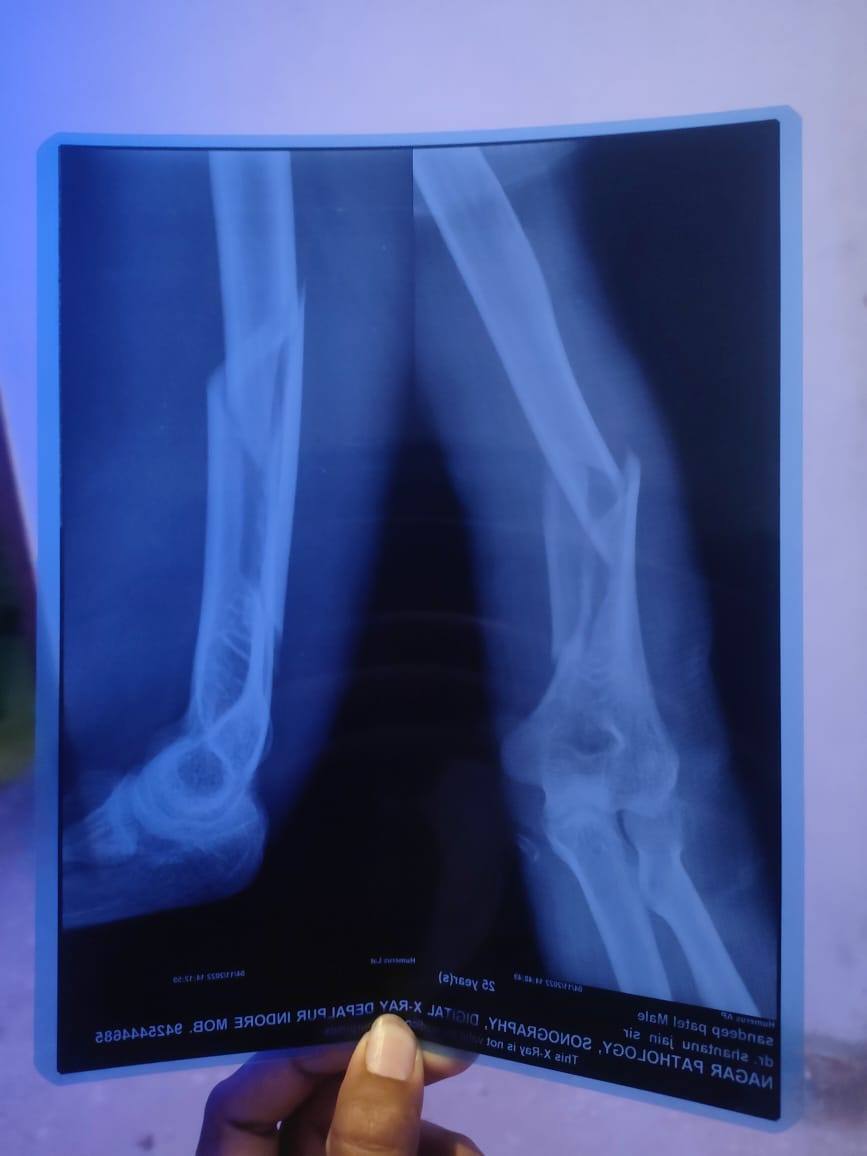

Yes sir , arm wrestling me tuta tha ye,23 din ho gaye fracture ko, stitches bhi kat Gaye 5 din pahle , par sir bahut se qn he •Me gym kab se continue kar paunga •Or kitni strength vapas aa payegi pahle k comparison me •Or kab plate nikal payegi vapas •Or iske long term me kya issue ho sakte he ,

sergery to sahi Hui hena pic attached